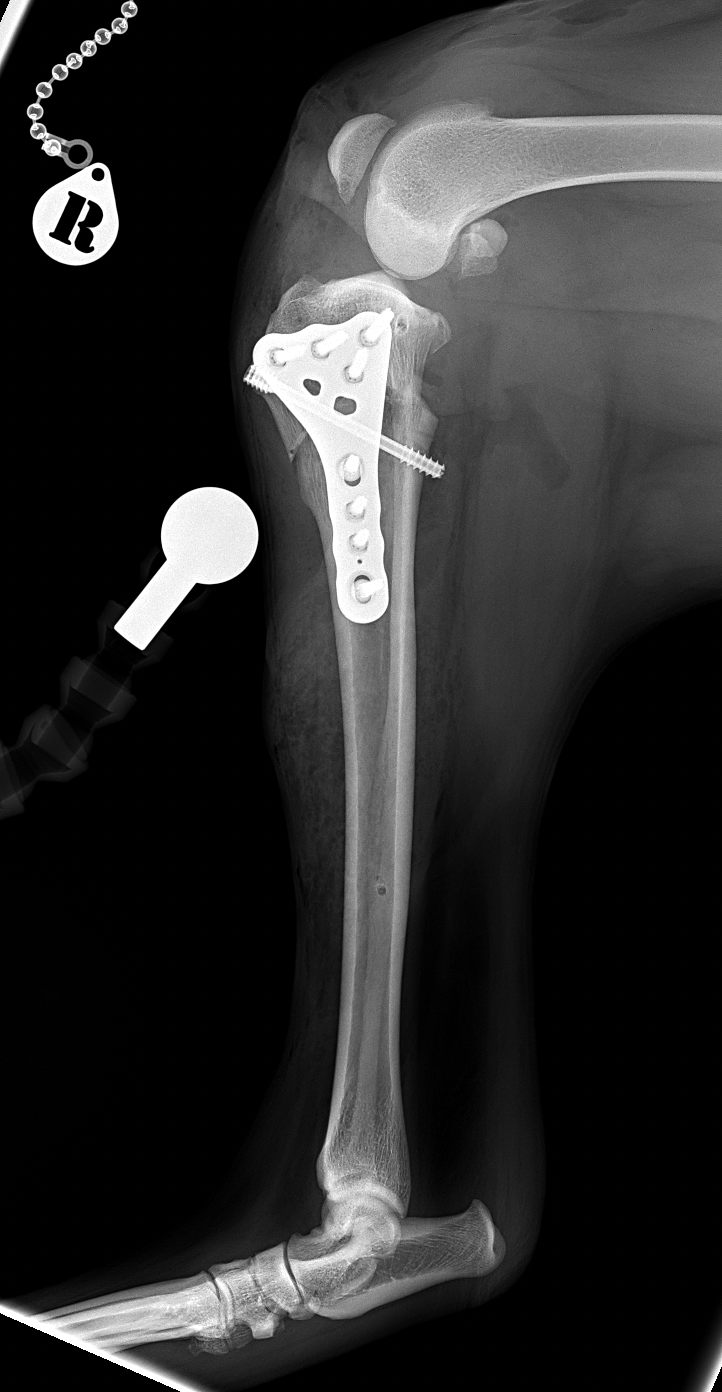

CBLO #241 超大型犬の前十字靭帯断裂に対して、Rita Broad 3.5 CORA Based Leveling Osteotomyで対応しました。しばらく安静が必要ですが、またドッグランで走れます。 症例カテゴリー 放射線治療整形外科軟部組織外科脳神経外科内科腫瘍外科救急・集中治療リハビリテーション科腫瘍内科内視鏡科脳神経科呼吸器外科中医・漢方猫の腎移植循環器科